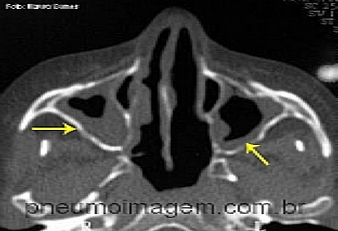

Veja imagens sobre sinusites no PneumoImagem,

clicando aqui.